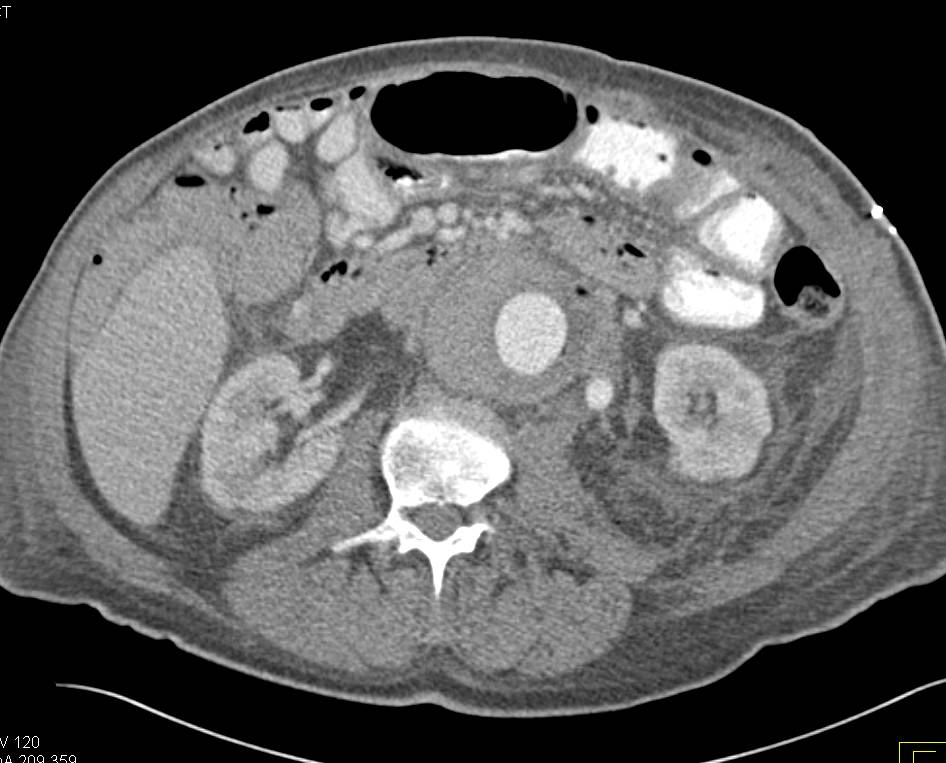

Aortic Aneurysm with Aorto-Enteric Fistulae. Note the Air in the Aortic Sac.